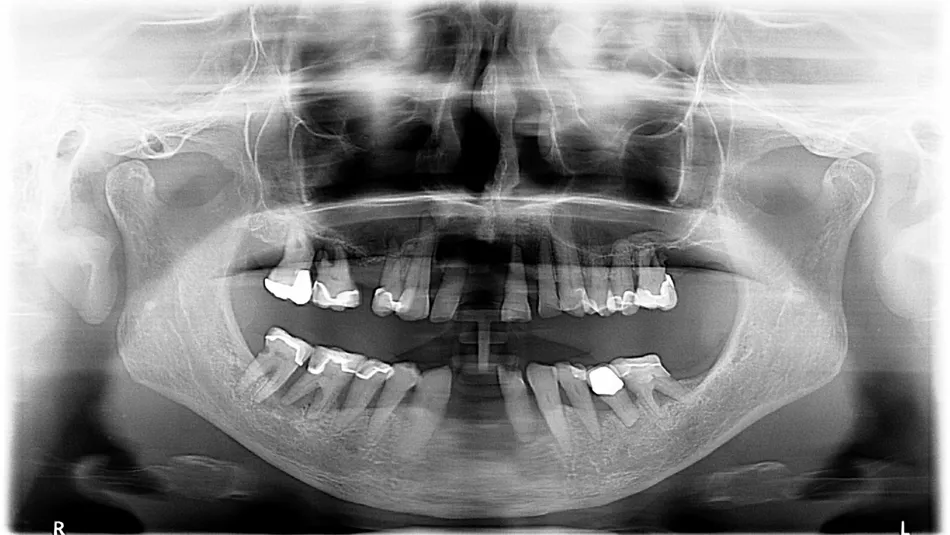

1.Pre-operation radiograph:

Clinical examination with x-ray showing a poor prospective for long-term prosthetic life of teeth on the lower jaw. In the upper jaw, teeth 13, 12, 22, 23, 24 and 25 were permanently preserved following preliminary treatment.